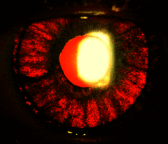

The authors conducted a literature review about bilateral acute iris transillumination (BAIT) syndrome, a new and relatively unknown syndrome that should be described and made known to the greatest number to avoid potential diagnostic and therapeutic errors. The first cases date back only to 2004 and a total of 79 cases have been published to date, mainly in Europe and especially in Turkey and Belgium. It mainly affects young women between the ages of 30 and 50, and symptoms are often preceded by an upper airway infection. There is also a majority of cases where the onset of the syndrome follows oral intake of moxyfloxacin. The clinical signs are dominated by strong photophobia, secondary to a spectacular transillumination of the iris. Other classical symptoms are conjunctival infection, eye pain, blurred vision, temporary ocular hypertonia, fixed mid-dilated pupils, and pigment dispersion in the anterior chamber with pigmentary deposits in the trabecular meshwork in gonioscopy, symptoms that may be mistaken for uveitis. After a few weeks or months of evolution, persistent sequelae were pupillary atony and chronic and bilateral transillumination of the iris, leading to significant photophobia and sometimes persistent ocular hypertension. The BAIT syndrome is close to the bilateral acute depigmentation of the iris (BADI) syndrome, which is similar to BAIT but lacks associated transillumination. A few cases of patients with BAIT syndrome on one eye and BADI syndrome on the contralateral eye have been described, which confirms some form of link between the two clinical entities.